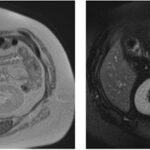

Paciente femenina de 48 años de edad que ingresa a Hospital Sanatorio Franchin por síntomas de cefalea y mareos, cuadro que se hace progresivo, presentando síncopes y posteriormente alteración del estado de conciencia. Los exámenes clínicos revelan una glucosa de 40 mg/dl, concomitante con insulina alta y péptido C elevado. Ingresa de forma programada para realización de duodeno pancreatectomía el 29 de mayo de 2021. Imágenes diagnósticas muestran estudio trifásico de tomografía de abdomen, lesión nodular en la cabeza del páncreas con ávido realce en fase arterial que en resonancia magnética se observa hiperintensa en T2, presenta restricción con la difusión y caída de la señal en el ADC. Además presenta realce tras la administración de contraste con gadolinio.

La resonancia magnética es el otro estudio de imagen no invasivo que nos permite la detección de la lesión con una sensibilidad mayor que la de la tomografía, del 85% al 95%, donde los insulinomas presentan un realce tras la administración de contraste con gadolinio y secuencias T1 sin contraste son lesiones hipointensas y en secuencias T2 son hiperintensas.

La resonancia magnética confirmó aún más el diagnóstico de las lesiones ya previamente visualizadas en tomografía en esta revisión, con realce de las lesiones en secuencias T1 y contraste con gadolinio, y en las secuencias funcionales con restricción de la lesión y caída de la señal en el mapa de ADC.